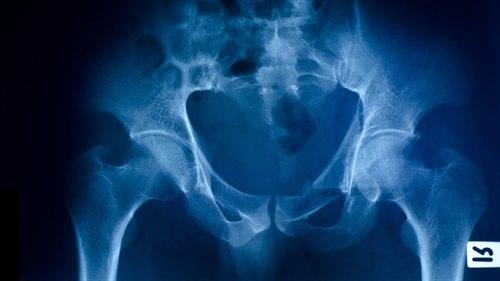

Bekkenet med hofteleddHofteleddet er et kuleledd som består av leddkule (lårbeinshodet) og leddskål (acetabulum). Leddflatene til lårbeinshodet og acetabulum er kledd med leddbrusk. Hofteleddet har en betydelig bevegelighet i alle plan og stabiliseres av leddkapselen, omgivende muskler, bruskskålen som kler den benede leddskålen og en bruskkant (labrum) som forlenger bruskskålen og stikker noen millimeter ut over den beinede kanten av hofteskålen. Labrum gjør dermed leddskålen dypere, gjør leddet stødigere og beskytter leddet.